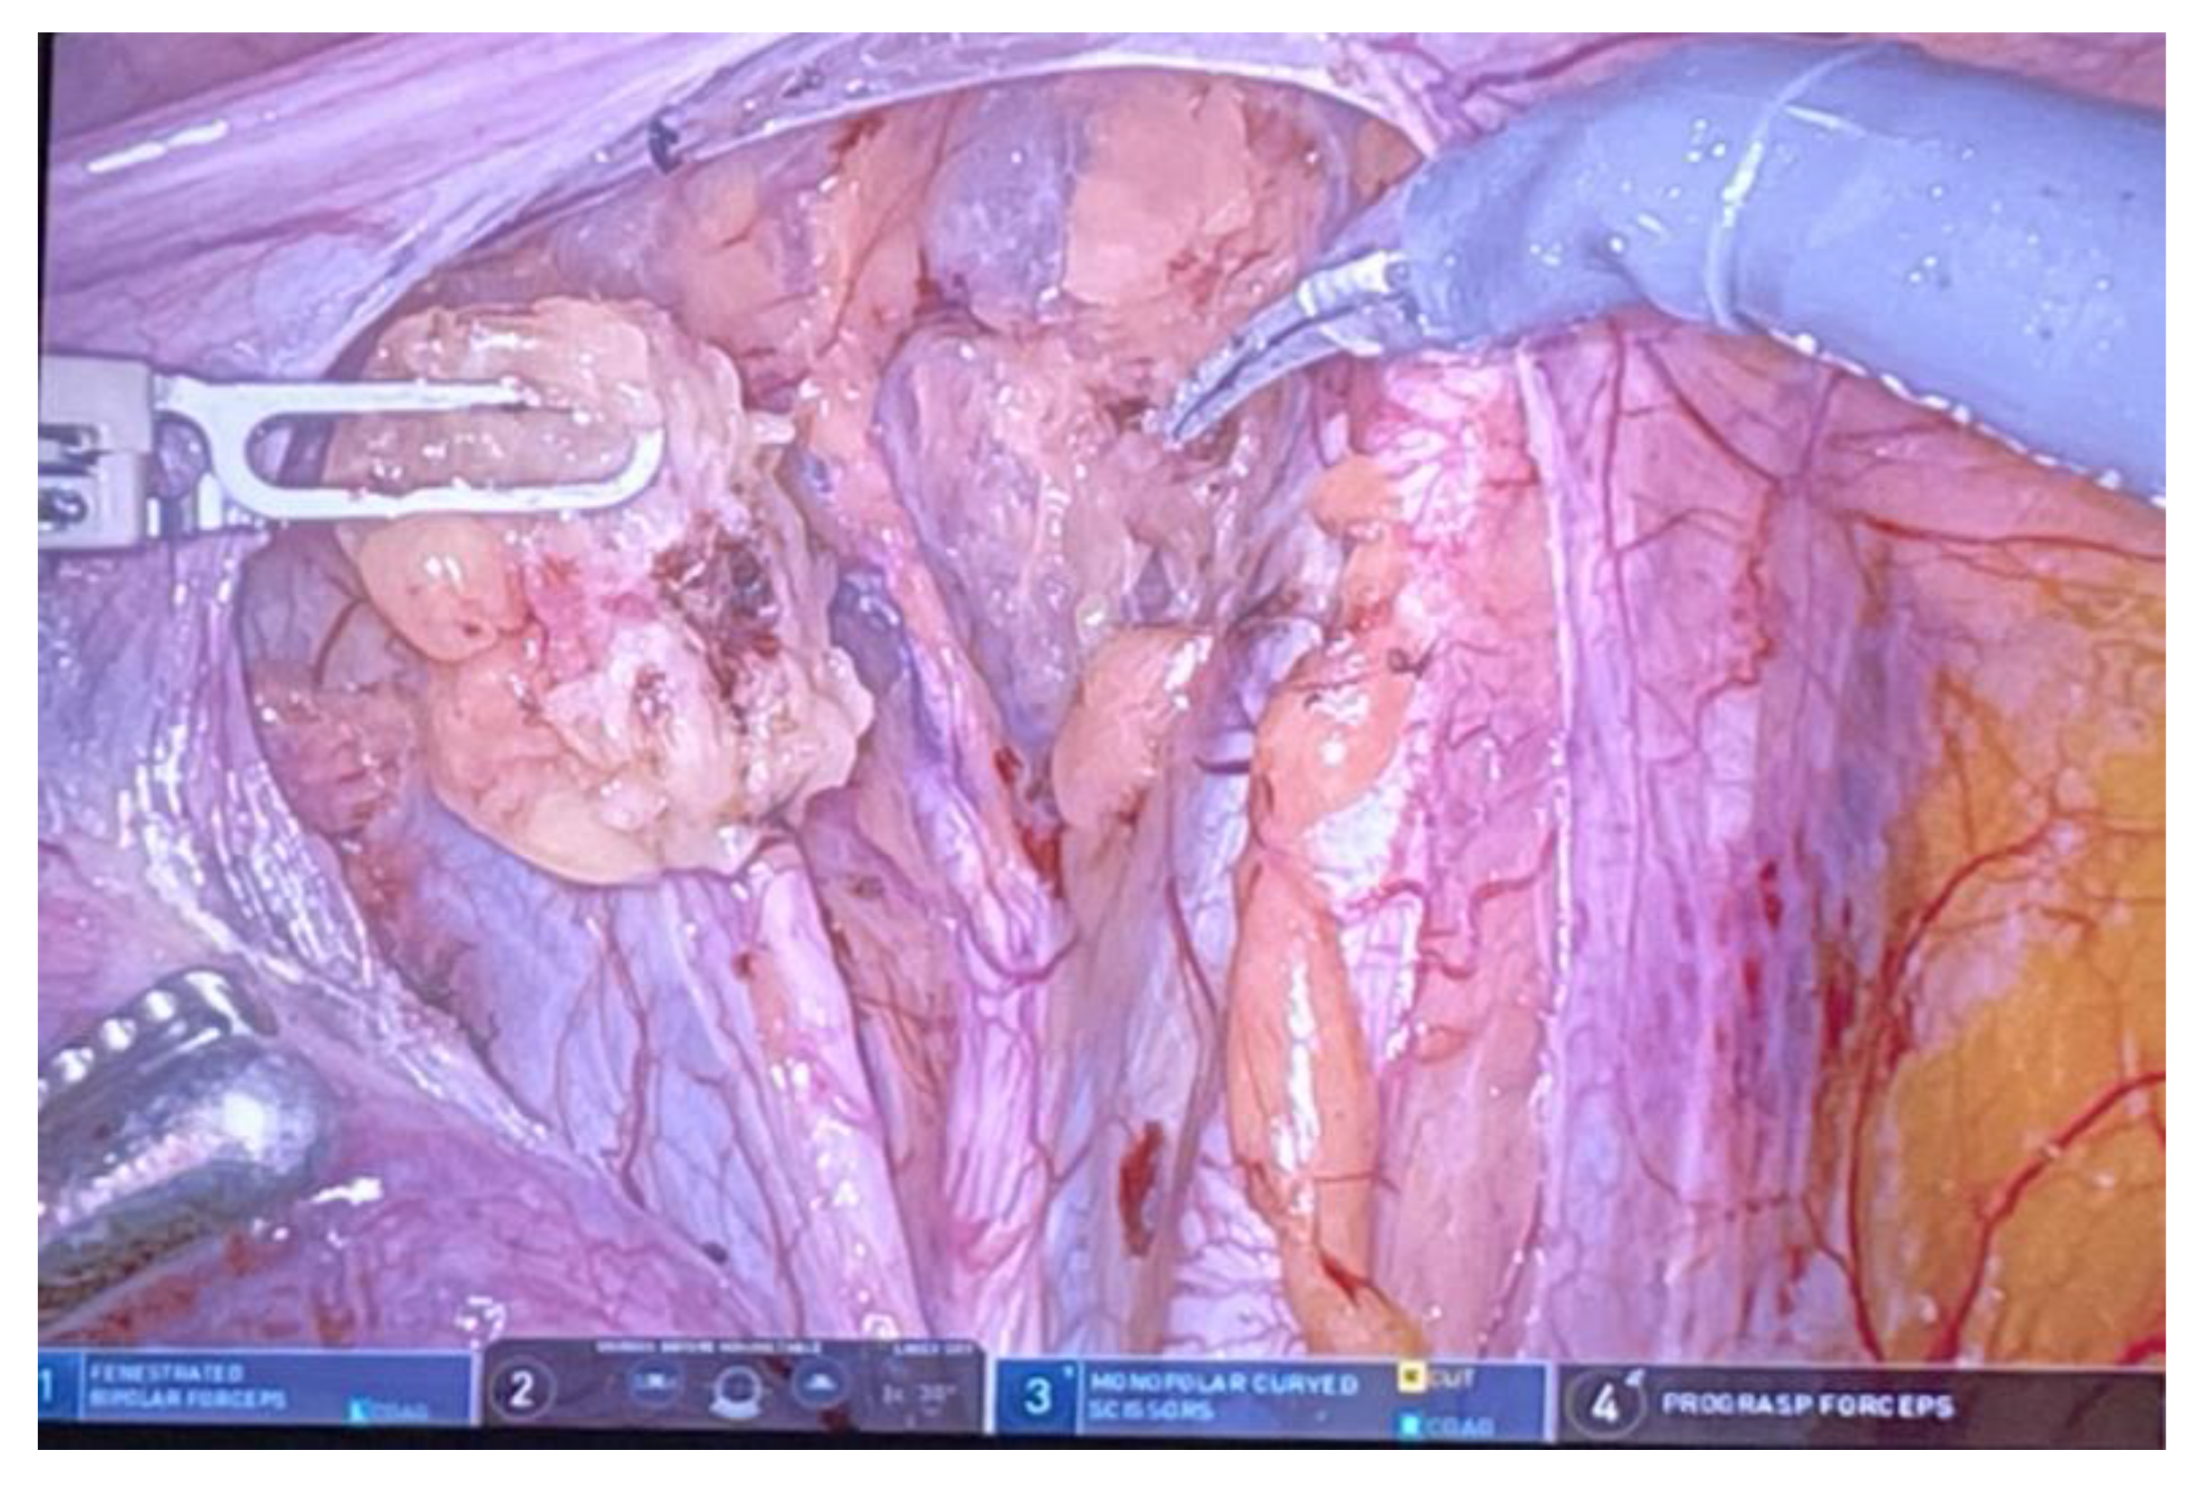

3.7. Robotic Surgery in Endometrial Cancer

3.8. Benefits of Robotic Surgery at a Young Age